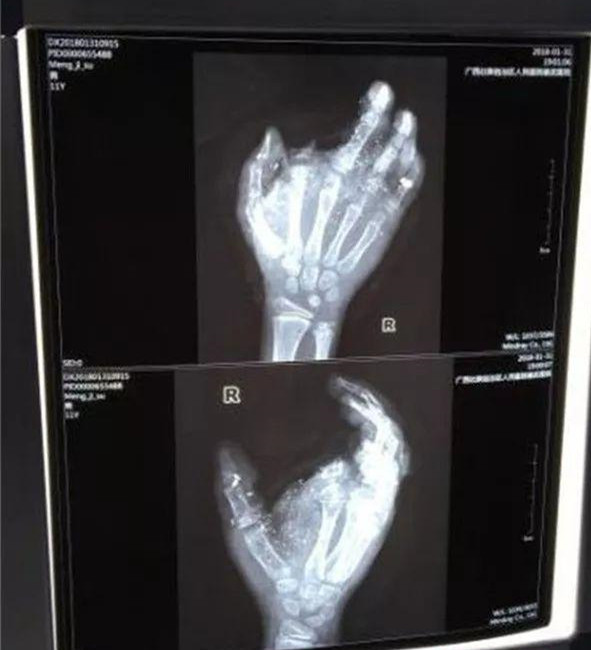

手機(jī)爆炸,12歲男孩手指被炸沒,寒假應(yīng)該注意哪些安全隱患

寒假來了,相信很多孩子都會(huì)在家拿著爸爸媽媽的手機(jī),沉迷在游戲的世界里,家長你知道嗎?這看似很平常的事情卻暗藏危機(jī)。事例,...